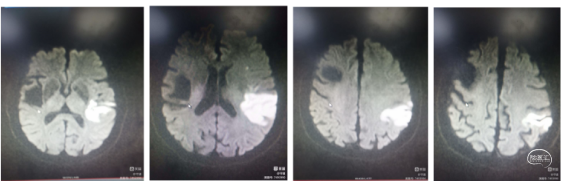

病例简介:患者老年女性,76岁,“突发意识模糊,右侧肢体无力2小时”入院。查体左侧肢体肌力2级,心房颤动,NIHSS评分9分。CT无出血征象。急诊核磁DWI:左侧大脑半球高密度。

诊断:1.心源性栓塞可能;2.左侧大脑中动脉下干急性闭塞。

核磁DWI示:左侧大脑中动脉区域大面积梗塞(发白的区域)。

病因:血管狭窄并梗塞可能(左侧大脑中区域较右侧萎缩)。似乎低灌注表现(DWI密度不均,大部分密度不太高)。